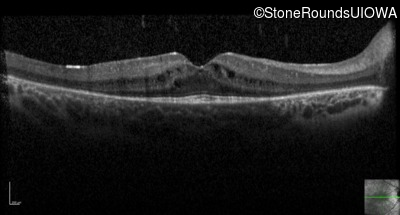

Optical Coherence Tomography - Left - 20/40 -1

Exemplar / OCT Stack